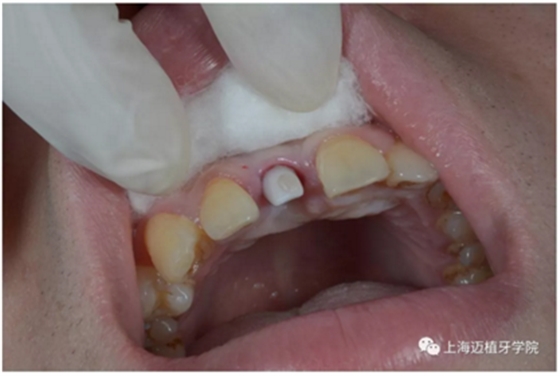

轉(zhuǎn)移模型

取工作模型

比色:3/M2

氧化鋯個(gè)性基臺(tái)